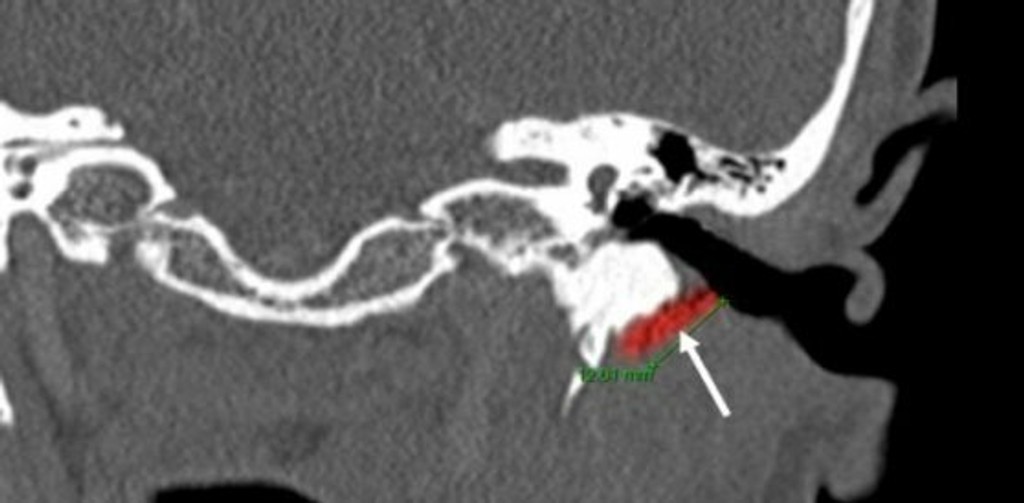

Austrálska lekárka vytiahla z ucha jedného pacienta dvojcentimetrového žijúceho švába, ktorý sa dostal do zvukovodu a spôsoboval mužovi veľké bolesti. O prípade dnes informovala tlačová agentúra DPA.

Doktorka použila starý domáci spôsob a naliala pacientovi do ucha olivový olej, avšak šváb najprv zaliezal hlbšie. Prestal až po desiatich minútach, vybrali ho pinzetou. Lekárka povedala, že z ľudského ucha ešte nikdy nevytiahla takého veľkého živočícha.